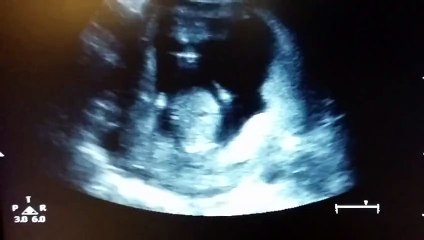

Une échographie montre un bébé frapper dans ses mains

Duration: 00:16